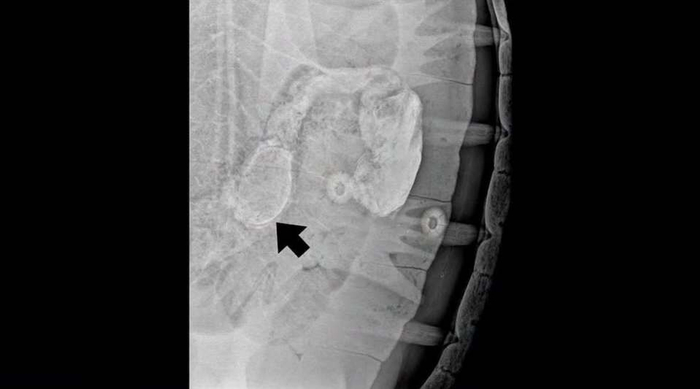

经检查确认,该异物位于海龟的消化道内。

工作人员对这只海龟的健康状况进行了27天的密切监测,直至上周四它终于成功排出这条20厘米长的腕带。